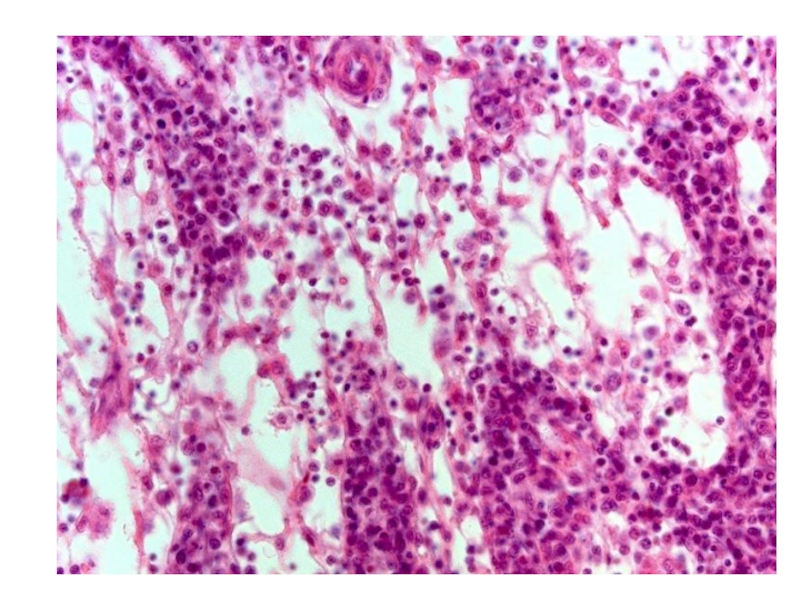

Слайд 47Препараты №60 и №61 «Плотная неоформленная волокнистая

соединительная ткань. Срез

кожи пальца»

Препараты №60 и №61 «Плотная неоформленная волокнистая соединительная ткань. Срез кожи пальца»